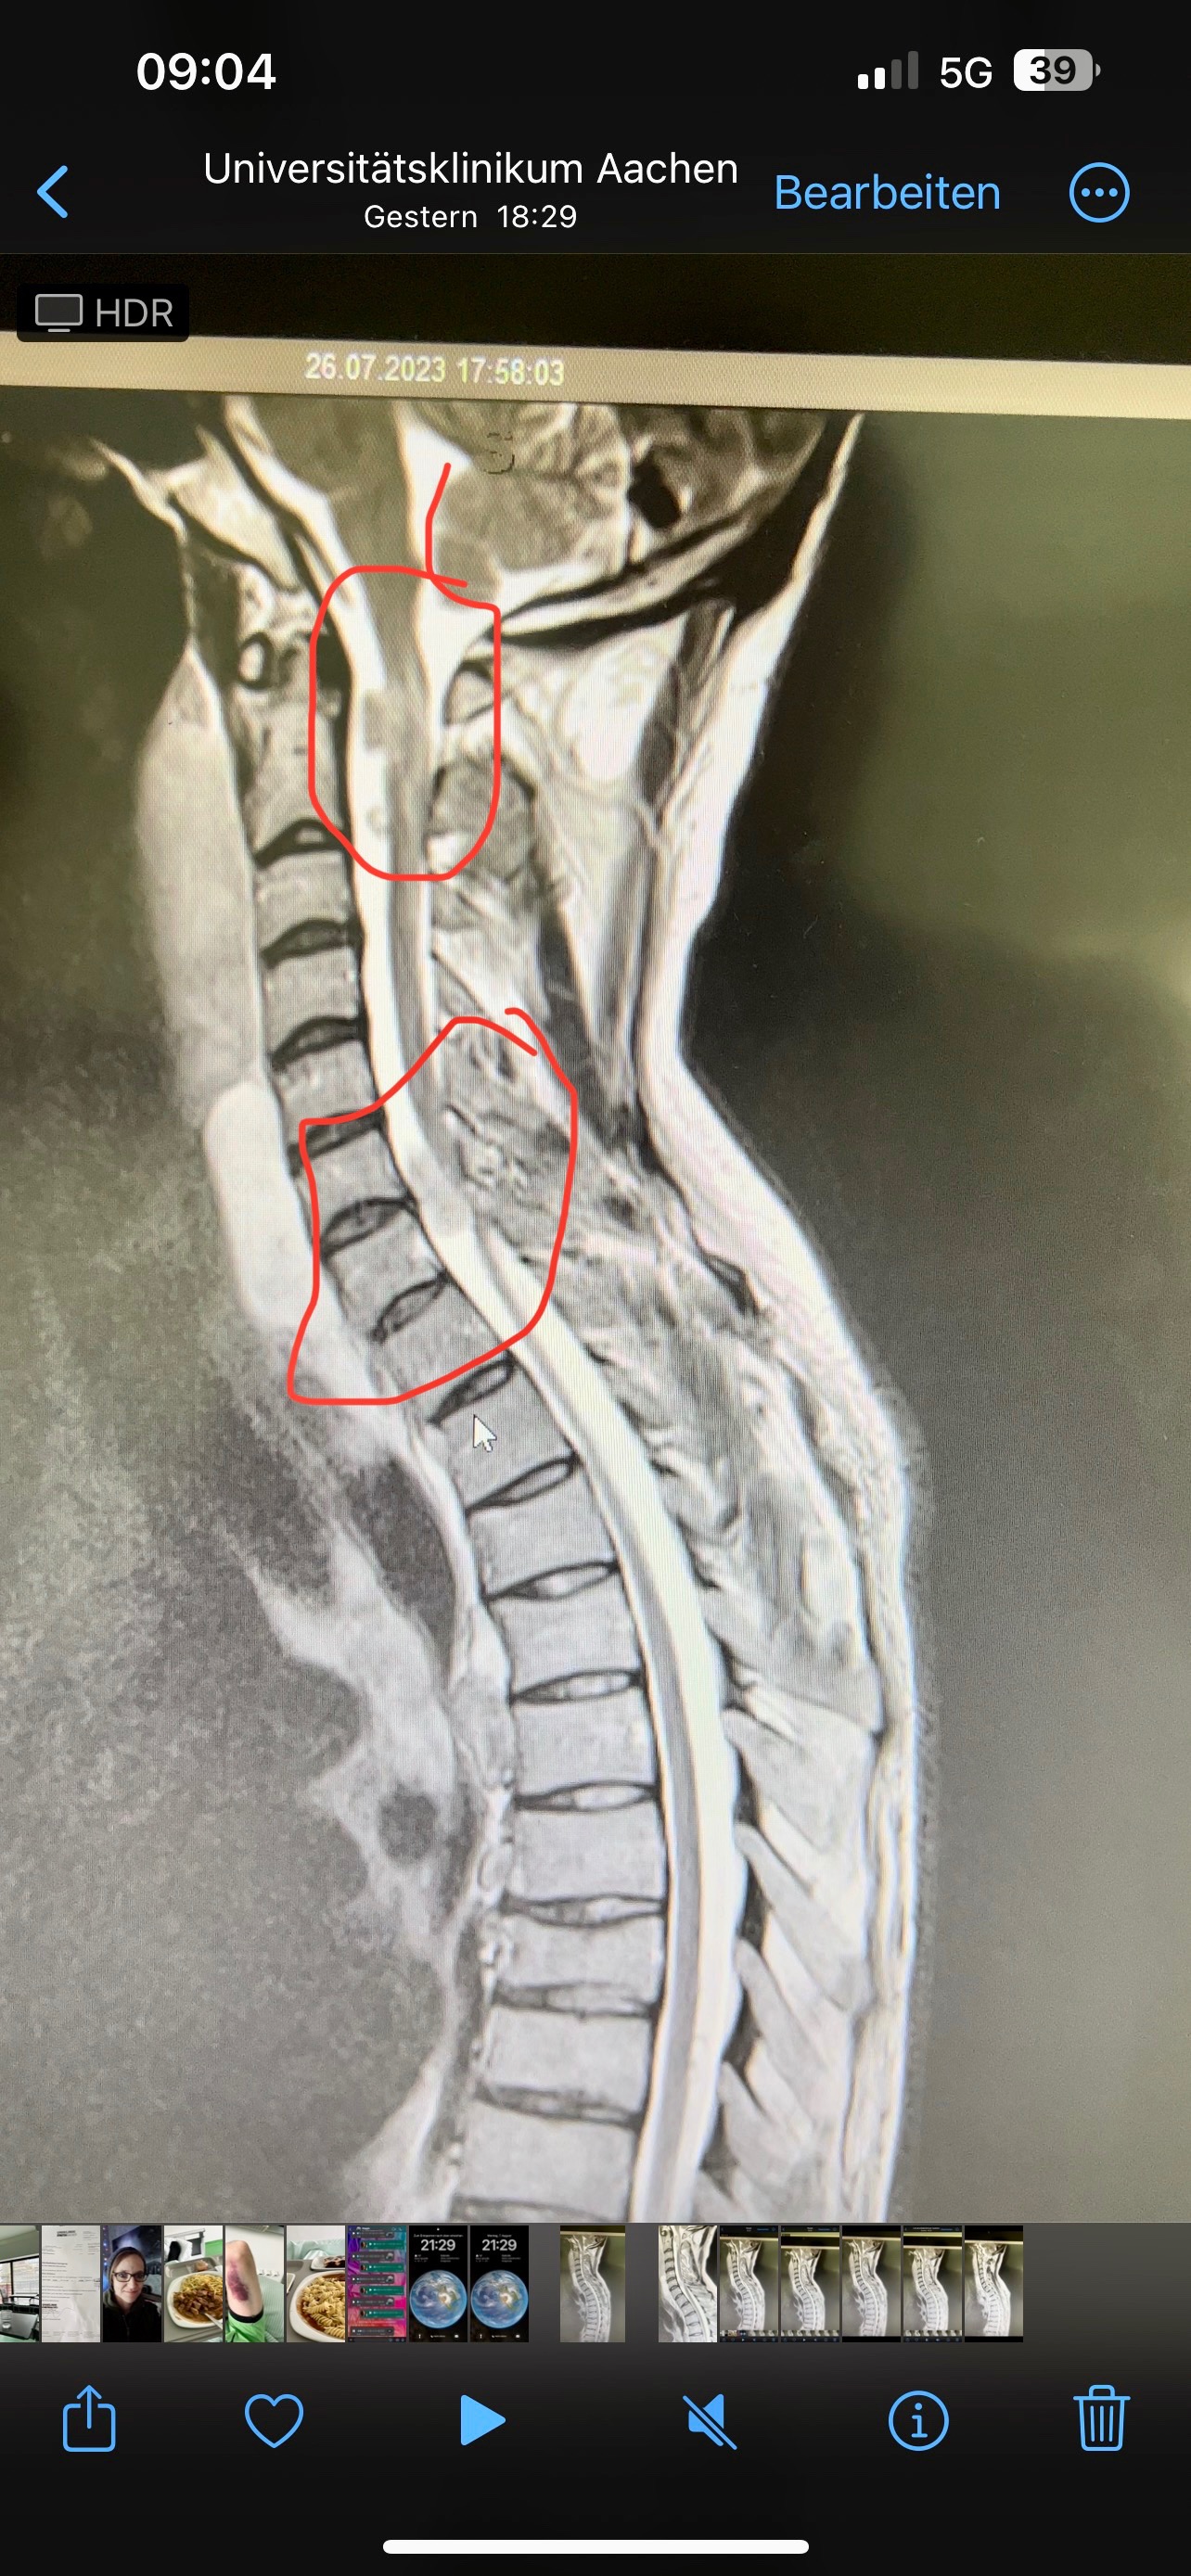

Transparenz Auf Wunsch stelle ich gerne zur Verfügung: • Ärztliche Berichte • MRT-Bilder • Kostenvoranschläge und Rechnungen Diese Unterlagen kann ich euch gerne per E-Mail oder WhatsApp zusenden – damit ihr wisst, dass eure Hilfe gut aufgehoben ist.

My Condition I suffer from Neurofibromatosis Type 1 (NF1), a genetic neurological disorder that causes benign tumors to grow along the nerves. When these press on nerve pathways, they can lead to severe pain and neurological impairments. In August 2023, after a fall, I had to undergo major spinal surgery. Two tumors were removed. Since then, I have been partially paralyzed. I do not have complete paraplegia – I can still move my legs – but I am no longer able to walk independently. In addition, my left hand is slightly impaired. This means that in everyday life I constantly rely on aids and can no longer manage many things on my own. Every small distance requires strength, courage, and determination. Still, I try every day not to give up and to regain as much independence as possible.

Transparency Upon request, I am happy to provide: • Medical reports • MRI images • Cost estimates and invoices I can gladly send these via email or WhatsApp so you know your support is truly making a difference.